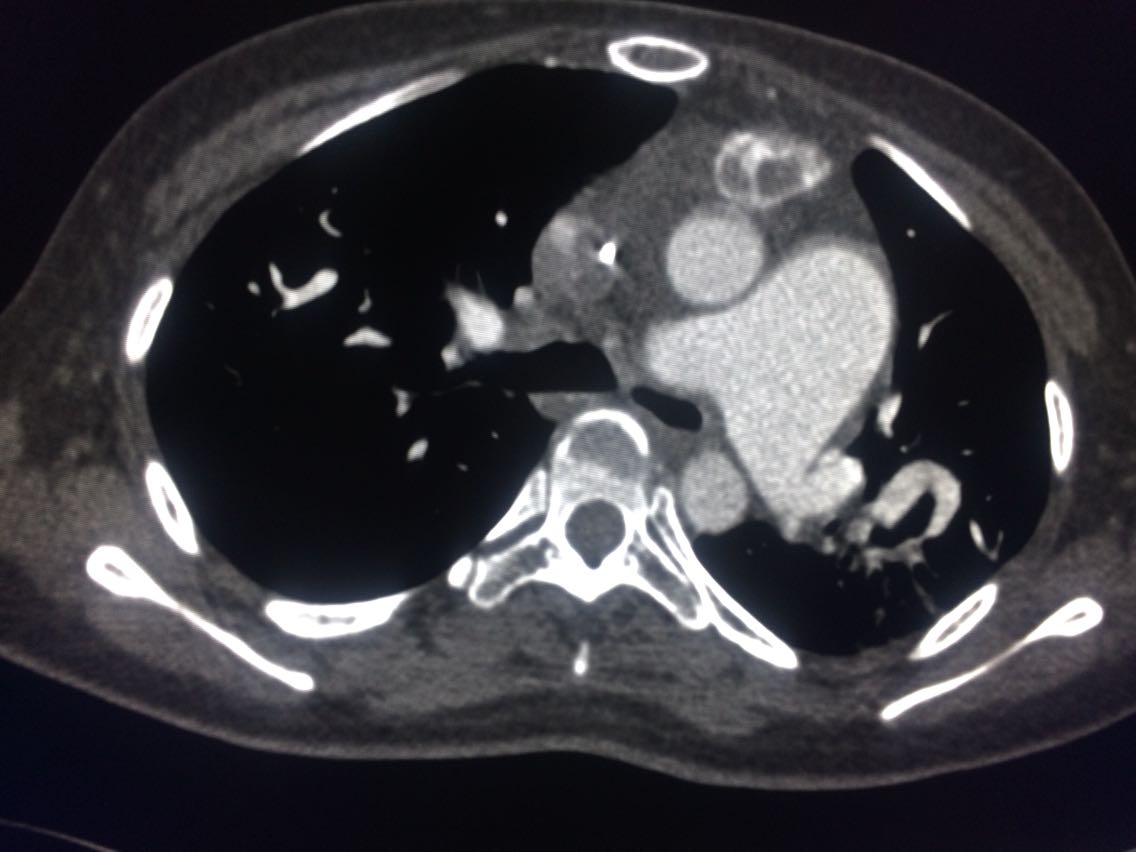

诊断,肺动脉高压。 鉴别诊断,肺动脉栓塞。 影像诊断,肺动脉高压,肺门区出现残根征,肺动脉扩张,肺动脉段膨隆,心影增大。CTA见迂曲增宽的肺动脉。 肺栓塞,影像可见典型充型缺损影,伴随肺纹理的减少。 治疗以对症处理为主,病人病史14年。 讨论诊断和鉴别诊断? 随访,症状好转。